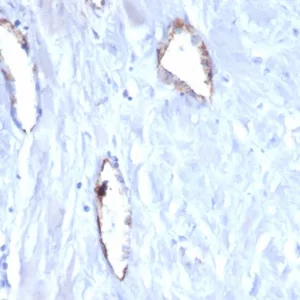

Immunohistochemistry is a technique used to detect and visualize specific proteins or antigens within tissue sections, typically from formalin-fixed, paraffin-embedded (FFPE) samples. Immunohistochemistry provides valuable information about localization, differential expression, tissue morphology, and disease pathogenesis. IHC provides quantitative data for validating the presence of a specific protein of interest in tissue samples and antibodies. Overall, IHC is valuable for understanding protein localization, tissue structure, and disease pathology. It is widely used in research and clinical diagnostics for various applications, including cancer diagnosis, neuroscience, and developmental biology.